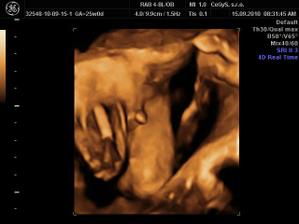

Náš anjelik🙂